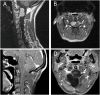

Background: Removal of anteriorly located tumors of the upper cervical spine and craniovertebral junction (CVJ) is a particular surgical challenge. Extensive approaches are associated with pain, restricted mobility of neck and head and, in case of foramen magnum and clivus tumors, with retraction of brainstem and cerebellum. Methods: Four symptomatic patients underwent resection of anteriorly located upper cervical and lower clivus meningiomas without laminotomy or craniotomy using a minimally invasive posterior approach. Distances of natural gaps between C0/C1, C1/C2, and C2/C3 were measured using preoperative CT scans and intraoperative lateral x-rays. Results: In all patients, safe and complete resection was conducted by the opening of the dura between C0/C1, C1/C2, and C2/C3, respectively. There were no surgical complications. Local pain was reported as very moderate by all patients and postoperative recovery was extremely fast. All tumors had a rather soft consistency, allowing mass reduction prior to removal of the tumor capsule and were well separable from lower cranial nerves and vascular structures. Conclusion: If tumor consistency is appropriate for careful mass reduction before removal of the tumor capsule and if tumor margins are not firmly attached to crucial structures, then upper cervical, foramen magnum, and lower clivus meningiomas can be safely and completely removed through natural gaps in the CVJ region. Both prerequisites usually become clear early during surgery. Thus, this tumor entity may be planned using this minimally invasive approach and may be extended if tumor consistency turns out to be less unfavorable for resection or if crucial structures cannot be easily separated from the tumor.